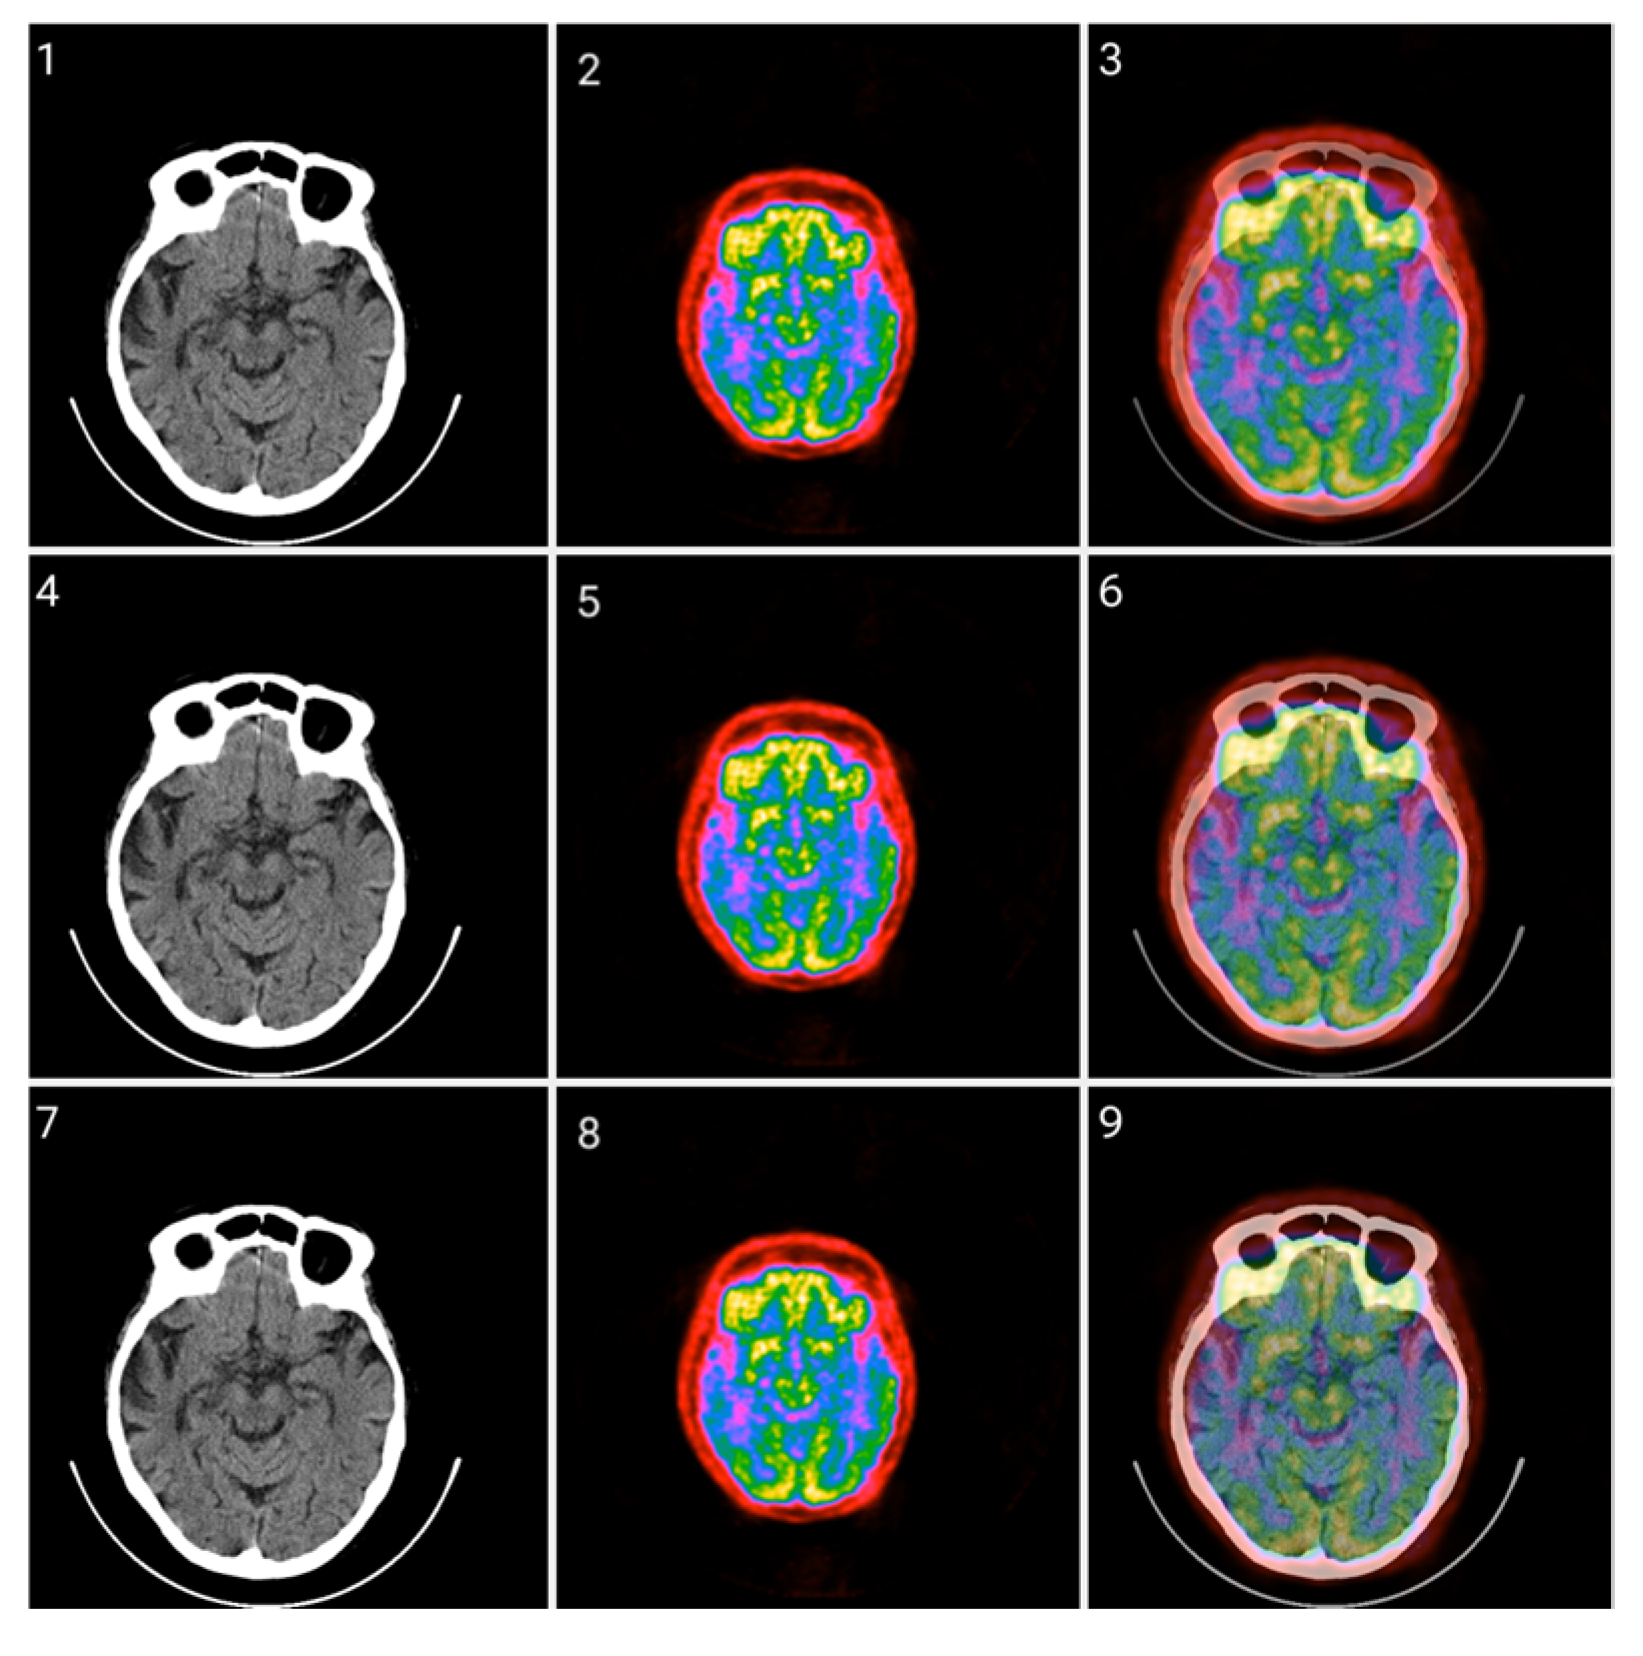

2.3. Method 2: Folding Colormap

3.2. Colormap Folding Application